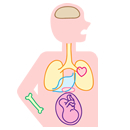

お口の中にある歯周病の原因菌が、お口から体内に侵入していって、病気や身体の器官に影響を与えていると考えられます。

歯周病と関係のある病気として、具体的には次のような病気が分かってきています。

・ 動脈硬化、心臓疾患

・ 糖尿病

・ 肺炎

・ 低体重時出産、早産

・ 骨粗しょう症、関節炎

・ 認知症